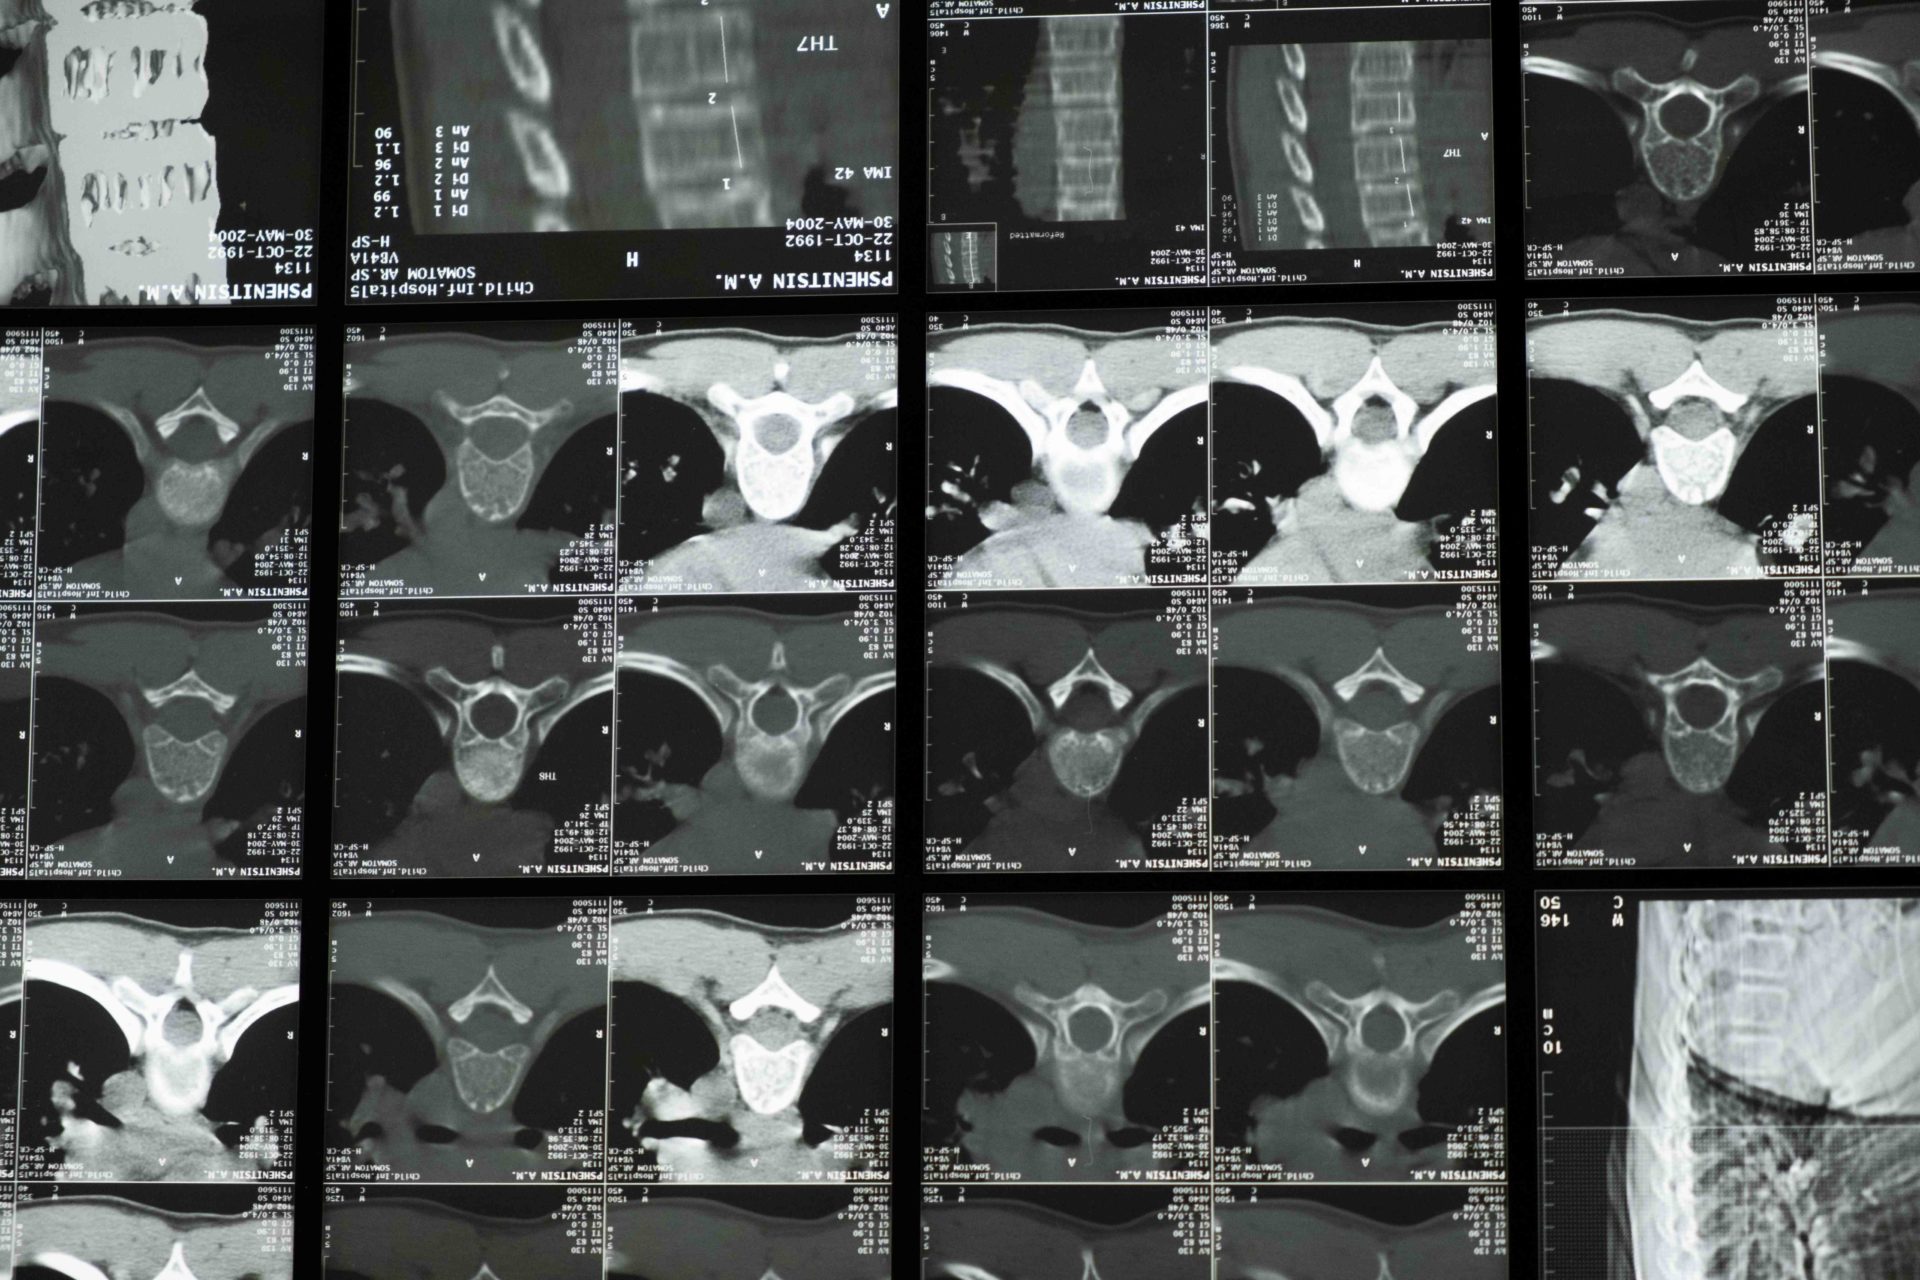

In the spine metastates can destroy bone in the vertebrae, weakening it and can cause significant spinal cord injury leading to paralysis.

Advanced computational modelling and imaging will be used to look at the growth of the tumour so that predictions of the strength of the vertebrae can be calculated a different points in time.